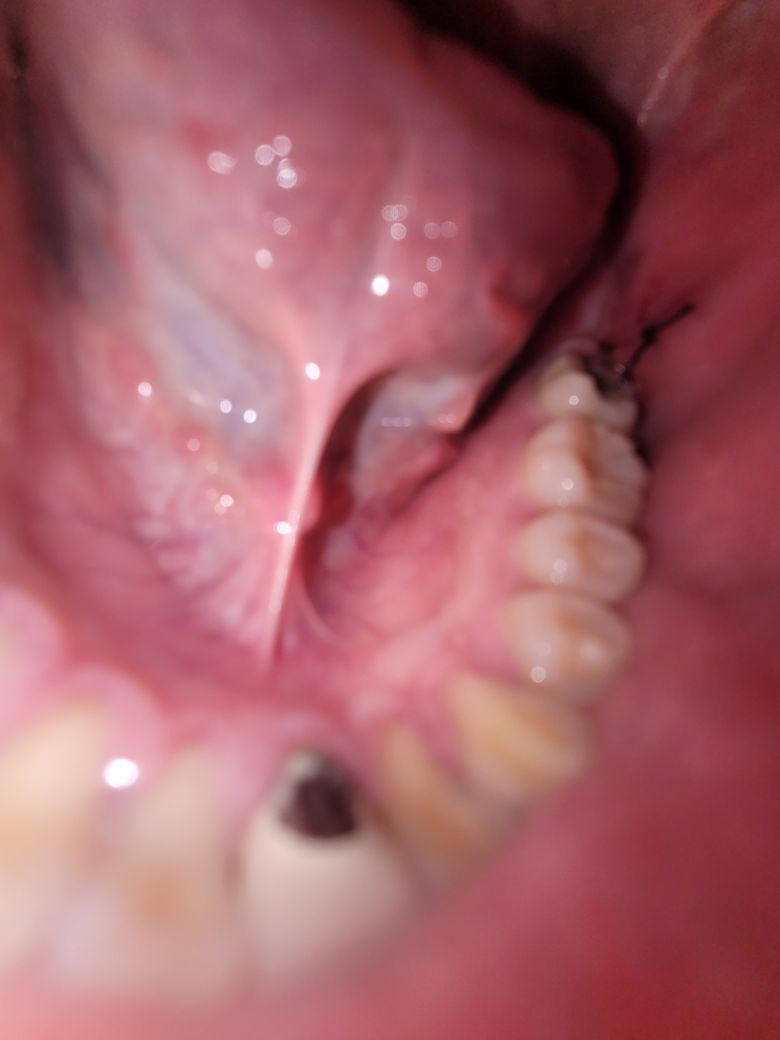

사랑니 발치 2일차인데 상태는 괜찮나요??

발치 2일차인데 얼음찜질하는도중 빠져나오는느낌이 들어서 보니

피딱지가 떨어진거같습니다.....

실밥 끝부분이 움직이는데 괜찮을까요....ㅠㅠㅠㅠ

사진상으로 크게 문제가 잇어 보이진 않습니다. 지혈이 잘되셧다면 삐딱지는 크게 문제가 없습니다. 걱정하지 않으셔도 될것같습니다.